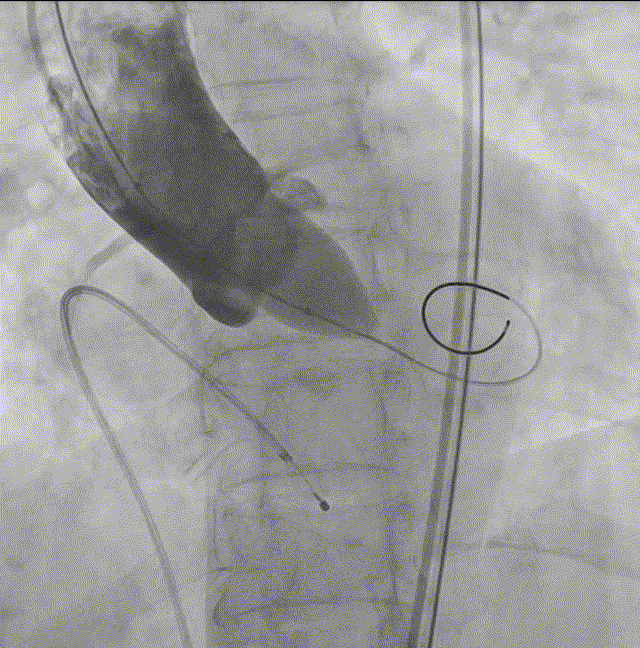

7. Silara A-23mm瓣膜过弓和跨瓣;

8. Silara A-23瓣膜左心室初步释放,瓣膜功能良好(不需要左心室快速起搏);

瓣膜释放

9. Silara A-23mm瓣膜提拉至瓣环水平,精准定位瓣膜,造影剂显示瓣膜功能良好,完成固化;